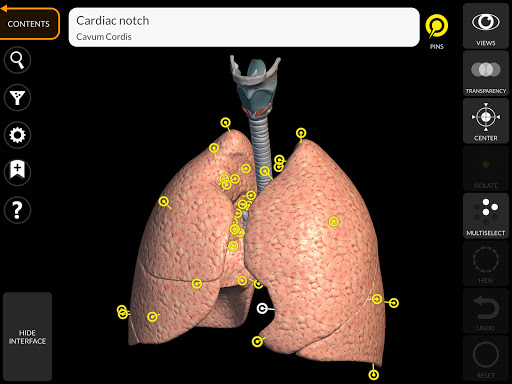

"Anatomy 3D Atlas" cho phép bạn nghiên cứu giải phẫu người theo cách dễ dàng và tương tác.

Thông qua giao diện đơn giản và trực quan, bạn có thể quan sát mọi cấu trúc giải phẫu từ mọi góc độ.

Các mô hình giải phẫu 3D đặc biệt chi tiết và có kết cấu lên đến độ phân giải 4k.

Việc phân chia theo vùng và chế độ xem được xác định trước giúp quan sát và nghiên cứu các bộ phận hoặc nhóm hệ thống riêng lẻ và mối quan hệ giữa các cơ quan khác nhau.

• Hệ thống hô hấp

• Hệ hô hấp